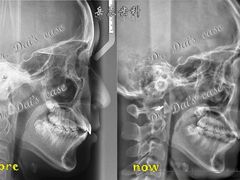

• 岳辰齿科(浦东长泰店)

• -岳辰齿科(浦东长泰店)

HH1002 | 22-08-10